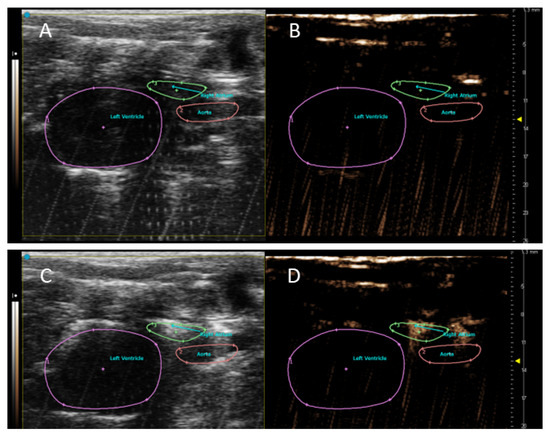

3.2. In Vivo NLC Imaging of Rat Heart